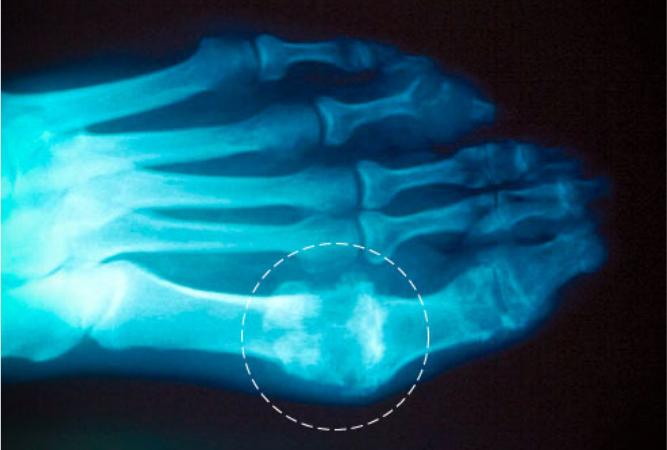

严重痛风的特点是患处关节开始时突然疼痛,接着就出现发热、肿胀、变红和变得非常敏感。大脚趾根部的小关节是病发的最常见部位。其他可能被感染的部位包括脚踝、膝盖、腰部、手指和肘部。一些患者的症状中,疼痛会非常剧烈——甚至到了床单碰到脚趾都会导致严重痛苦的程度。无论是否用药,这种发病的痛苦通常会在数小时到数天内结束。在一些少见的病例中,一次病发可以持续数周。大多数痛风患者都会在几年内经历反复的病发。

1、痛风的外在症状:大脚趾部位

大脚趾根部的关节是严重痛风最常见的病发位置。只要痛风没有治好,这个部位的症状就会复发。就算痛风的疼痛感已经消失了,也要去看大夫。随着时间流失,这种症状会损伤关节、肌腱和其他组织。